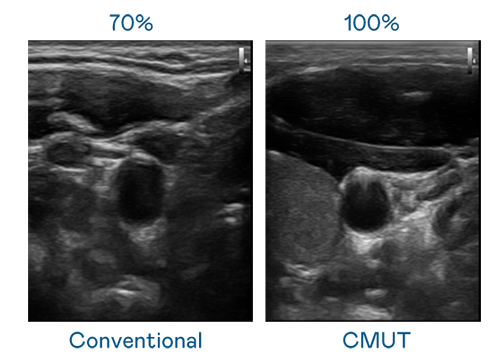

CMUT 技术是一种用电容式微机电元件来产生超音波讯号的技术。与传统 PZT 压电式技术相比,CMUT 频宽增加 30%,更宽频的超音波讯号让影像解析度大幅提升,是实现高影像品质医疗超音波扫描、促进精准医疗发展的关键技术。

超音波影像的解析度高低,首先取决于探头能发出的讯号频宽。尊龙·Z6 CMUT 可提供高清晰的超音波讯号,提供高频宽、高灵敏度、影像纹理细节更高的超音波影像,协助医护人员缩短影像判读时间及利用精准的医疗影像进行诊断。